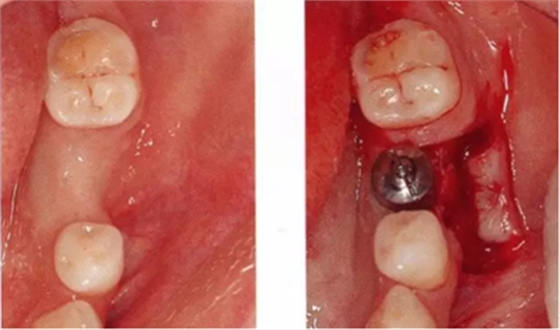

▲圖10-3,4

圖10-3 第二次手術(shù)前的(牙合)面照。

圖10-4 為了在頰側(cè)、舌側(cè)進行FGG,在上頜腭側(cè)采集大塊移植片

▲圖10-5,6

圖10-5 第二次手術(shù)后的舌側(cè)面照。遠中側(cè)進行APF,近中側(cè)進行FGG。

圖10-6 頰側(cè)也進行FGG,縫合后確認移植片不會移動。